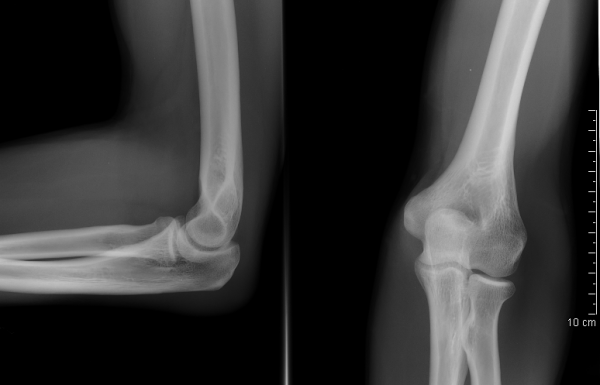

Инструментальные и лабораторные методы в диагностике эпикондилитов, как правило, не используются. Лишь в случаях явной травмы обычная рентгенография позволяет исключить костные повреждения (возможен перелом наружного надмыщелка), а нормальные лабораторные тесты (острофазовые показатели) исключают воспалительное заболевание суставов. При хроническом или часто рецидивирующем течении эпикондилита (что наблюдается крайне редко) на рентгенограмме можно видеть типичные для хронических энтезопатий изменения - разрыхления кортикального слоя, кистовидную перестройку костной ткани в области пораженного энтезиса и оссификацию энтезиса в виде «шпоры».

Здоровые локтевые суставы в передне-задней и боковой проекции

- Рентгенография.

- Данные анамнеза по возможности должны коррелировать с результатами рентгенографии.